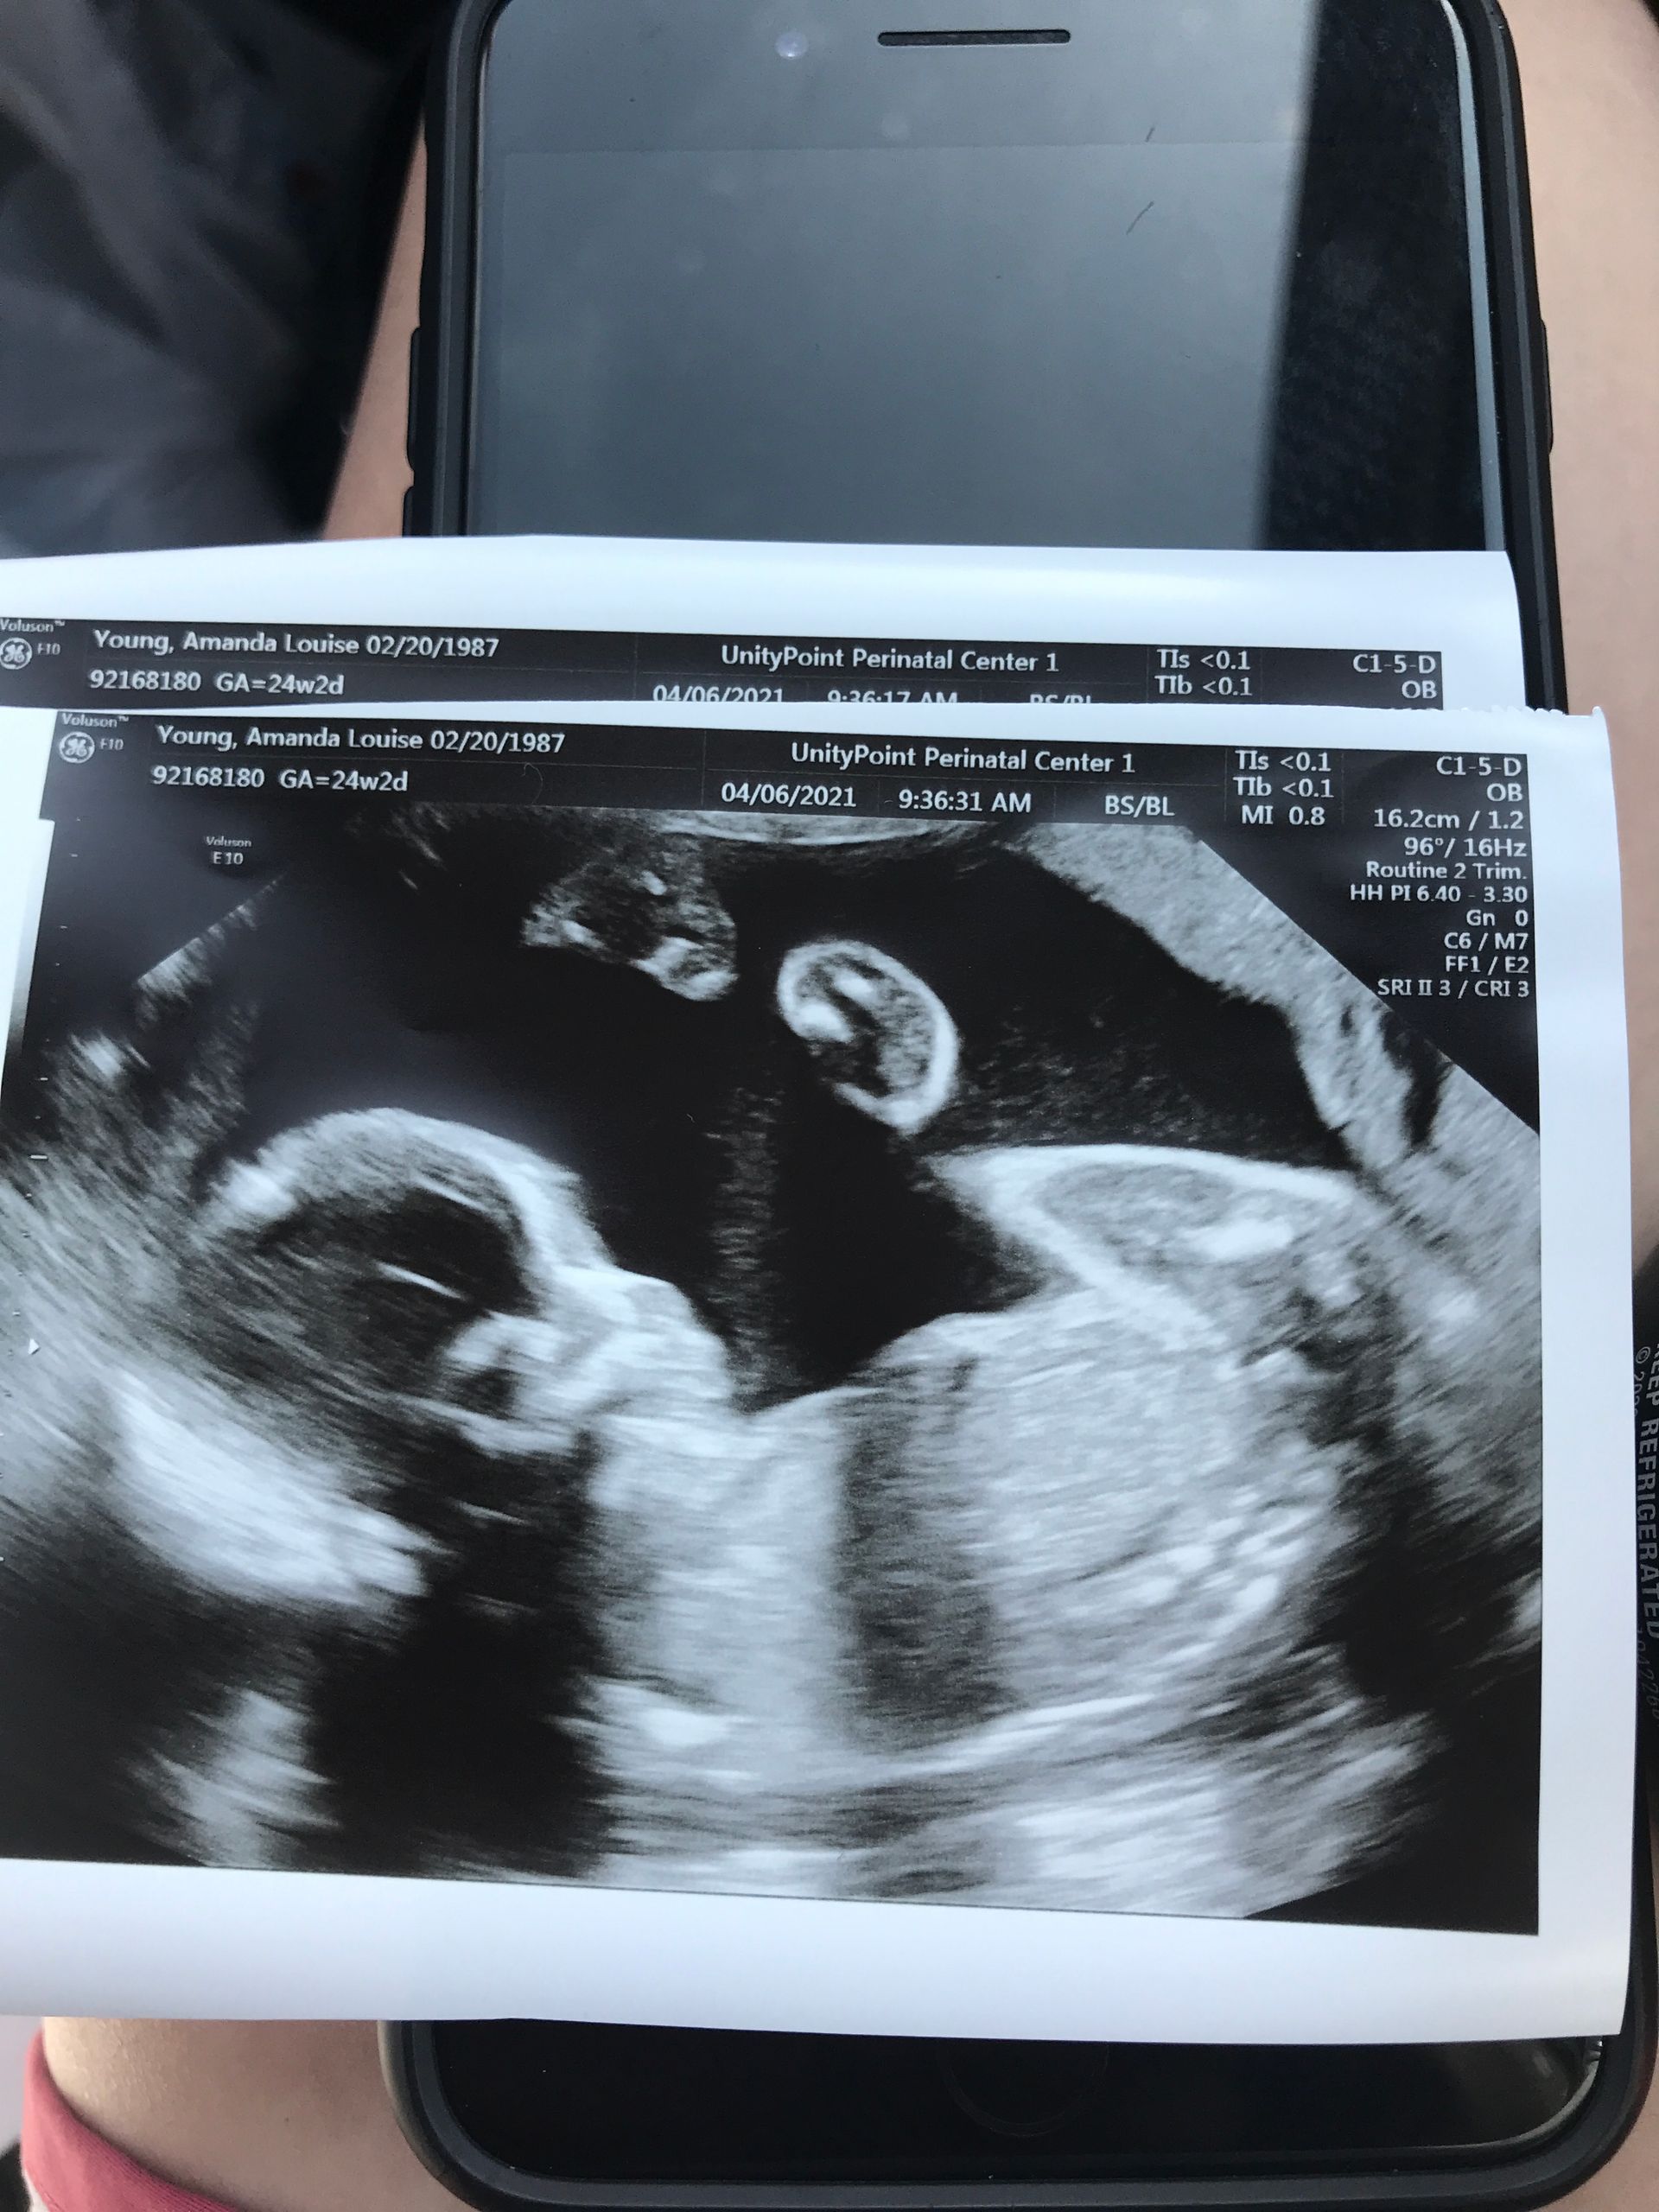

I am 24 weeks! I feel so much bigger already by this point. I am not sure how I am going to make it until July. I am going to be huge! I feel pretty good and this is my favorite time of pregnancy. We had our follow up ultrasound and baby is doing well! The heart all looks good and the placenta has moved a little but they are going to do another ultrasound closer to birth to make sure it is completely out of the way.

We got another ultrasound to make sure the placenta had fully moved and it has! We also got another look at baby girl! She is definitely smooshed in there!